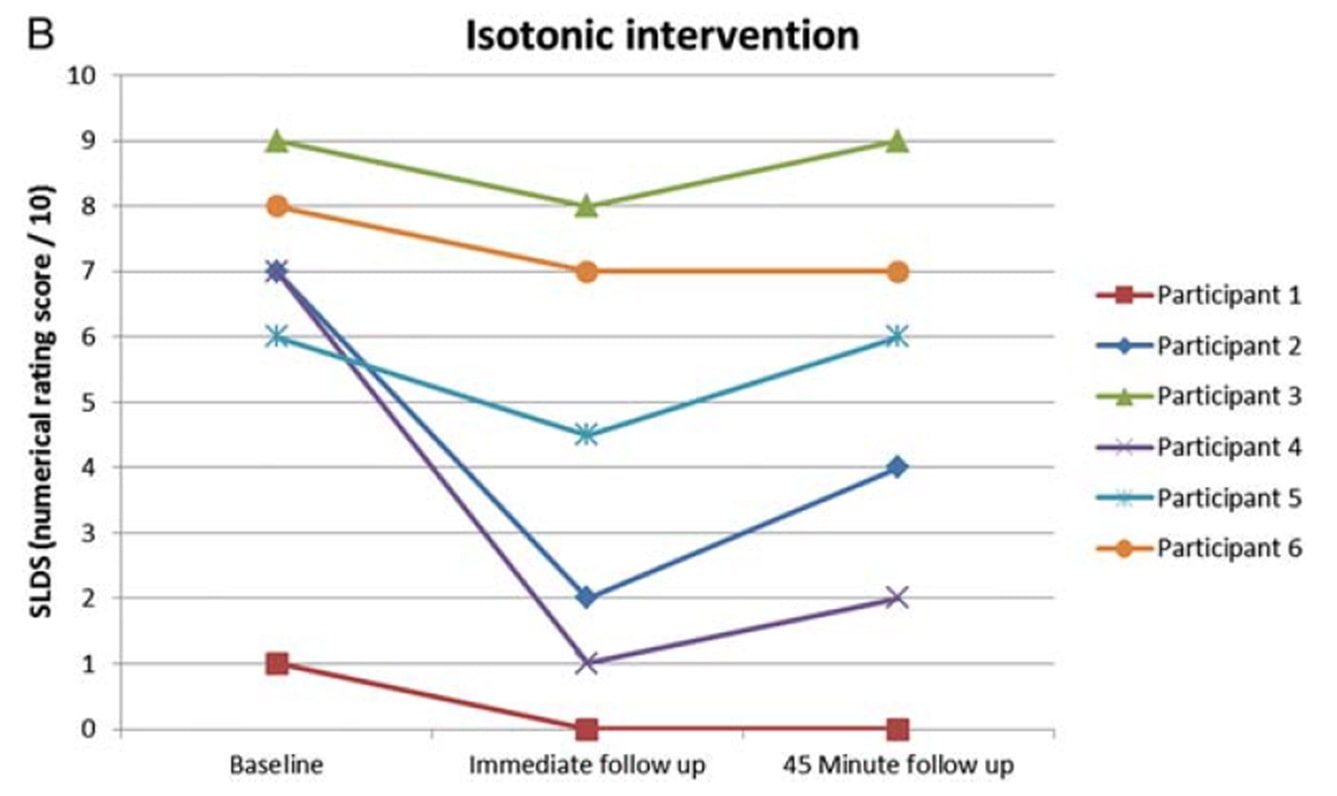

Río et al. (2015) iniciaron una pequeña tendencia cuando realizaron un ensayo cruzado en 6 jugadoras de voleibol con tendinopatía rotuliana. Sus resultados fueron sorprendentes, ya que todos los jugadores experimentaron una disminución inmediata del dolor, que pasó de una media de 7/10 en la escala NRS a 0, y sólo uno de los 6 informó de un dolor persistente de 1- durante al menos 45 minutos después de las contracciones isométricas. El protocolo que utilizaron fue de 5 series con 45 segundos de contracción en una máquina de extensión de piernas y un esfuerzo del 70% del esfuerzo voluntario máximo. También descubrieron que los isométricos eran capaces de disminuir la inhibición cortical y aumentar la fuerza en un 19%. Compararon la intervención isométrica con una intervención isotónica y los efectos observados en el grupo isométrico no pudieron conseguirse en el grupo isotónico:

Los mismos autores realizaron un estudio de seguimiento en temporada con atletas de salto dos años después (Rio et al. 2017) en el que compararon un programa isométrico y otro isotónico entre sí. En este estudio, los resultados fueron un poco más heterogéneos en ambos grupos, con una mayor disminución inmediata del dolor en el grupo isométrico: